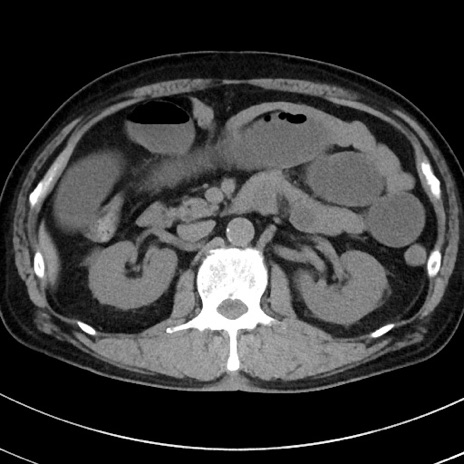

症例38(横断像)

【症例】70歳代 男性

【主訴】腹痛・嘔吐

【現病歴】昨晩より、嘔吐・腹痛あり。今朝になっても嘔吐あり。来院。

【既往歴】心臓バイパス手術、開腹胆摘、腸閉塞

【身体所見】BP 107/71mmHg、HR 116/min、腹部:平坦、軟、下腹部に軽度圧痛あり。反跳痛なし。

【データ】WBC 15100、CRP 0.32